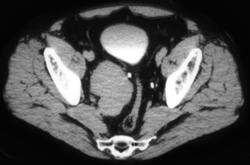

Transverse Process Fracture With Hematoma